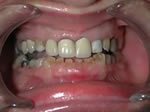

Full Mouth Reconstruction is the optimal choice when several teeth are decayed or missing, affecting the occlusion (the way the teeth come together) and/or the appearance of the face. Full Mouth Reconstruction may involve bridges, veneers, and/or crowns. Most of the existing teeth require treatment in order to correct and restore balance to the occlusion (bite) and facial features.